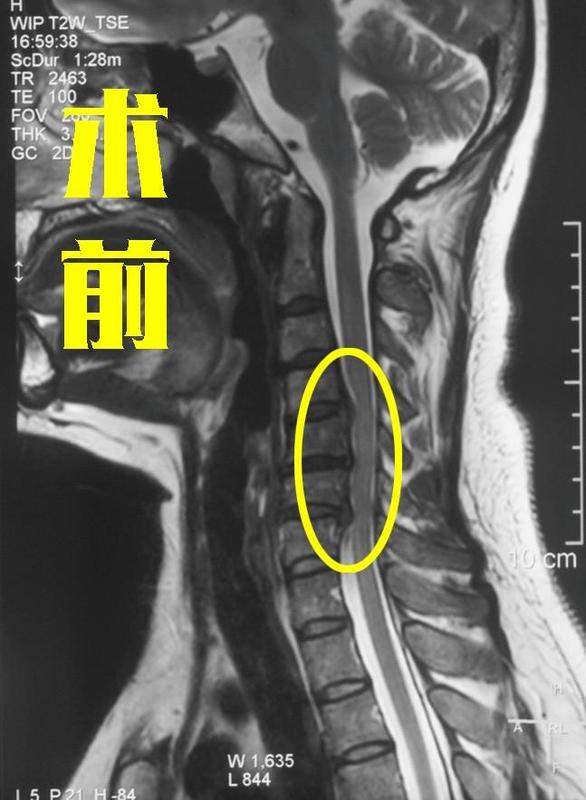

神經(jīng)根型頸椎病患者在各類頸椎病中的占比是非常高的,他們經(jīng)常會出現(xiàn)上肢放射性疼痛、麻木、無力等癥狀。這些癥狀往往讓患者痛苦不堪,尤其是不少患者反復(fù)發(fā)作,嚴(yán)重影響生活和工作。那有什么好辦法可以解決這個問題呢?近日,宣武醫(yī)院王作偉主任接診了一位50歲的男性患者。他在三年前就出現(xiàn)了頸部、右肩一直到右側(cè)胳膊的疼痛,當(dāng)時他就去了當(dāng)?shù)蒯t(yī)院就診,檢查出了神經(jīng)根型頸椎病。當(dāng)?shù)蒯t(yī)院給他開了一些營養(yǎng)神經(jīng)的藥物,他服用后確實(shí)癥狀減輕了不少。但誰知道好景不長,還不到半年的時間,癥狀再次出現(xiàn),這次他又嘗試了針灸、按摩,可是癥狀仍是反反復(fù)復(fù)。到了最近一段時間,他發(fā)現(xiàn)自己的疼痛加重,還出現(xiàn)了右手麻、無力的癥狀,尤其是大拇指、虎口特別麻,有的時候電腦辦公室時打字都受影響。這種多年的痛苦一直折磨著他,讓他已經(jīng)不能再忍受,為了徹底解決這個問題,這才請假來到北京,找到王主任。神經(jīng)根型頸椎病為啥會導(dǎo)致胳膊疼、手麻?王主任仔細(xì)觀察了這位患者的影像學(xué)片子,并給他做了詳細(xì)的查體,發(fā)現(xiàn)他的這些癥狀都是由頸5-6出現(xiàn)的椎間盤突出,壓迫到了右側(cè)神經(jīng)根所引發(fā)的。術(shù)前影像學(xué)資料:我們的頸神經(jīng)支配著頸部及上肢的運(yùn)動和感覺,若受到壓迫就會出現(xiàn)受壓神經(jīng)支配區(qū)域的放射性疼痛、麻木等癥狀。而且頸神經(jīng)分布有一定規(guī)律,基本上呈條帶狀,像這位患者的情況,頸5-6的椎間盤突出壓迫的是頸6神經(jīng),剛好他也出現(xiàn)了頸6神經(jīng)所支配區(qū)域的相關(guān)癥狀,還是比較典型的。除此之外,這類患者還常常伴有頸肩不適、手部握力減小等癥狀。神經(jīng)根型頸椎病患者反復(fù)出現(xiàn)胳膊疼、手麻,該怎么辦?一般來說,大部分的神經(jīng)根型頸椎病患者進(jìn)行保守治療后,癥狀就能得到明顯緩解。但是如果您像這位患者一樣,得病好幾年了,保守治療效果不好,癥狀反復(fù)發(fā)作,嚴(yán)重影響到平時的生活、工作,就需要考慮手術(shù)干預(yù)了。這種情況做手術(shù),效果好不好?王主任在得到這位患者的同意后,為其成功進(jìn)行了手術(shù)。術(shù)中將突出的髓核切除,給神經(jīng)根進(jìn)行了徹底的減壓。術(shù)后,患者立馬感覺到自己的上肢疼痛癥狀大大減輕,手麻也得到了明顯改善。折磨三年的病痛終于消退,他對治療效果很滿意。術(shù)后影像學(xué)資料:如果您也是神經(jīng)根型頸椎病,各種治療方法都試過了,癥狀仍是反反復(fù)復(fù),嚴(yán)重影響生活質(zhì)量,尤其還出現(xiàn)了手部肌肉力量下降、肌肉萎縮等情況,就不要再堅持保守治療了。這時手術(shù)可能是更好的選擇,術(shù)后您會發(fā)現(xiàn)生活質(zhì)量會得到極大改善。